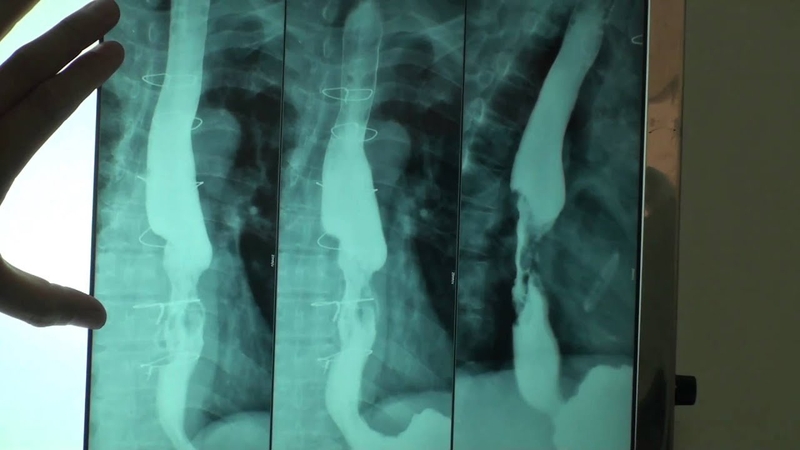

Tình trạng tụ dịch trong ổ bụng là một biến chứng nguy hiểm, thường xuất hiện trong các trường hợp viêm tụy cấp. Phương pháp chọc hút dịch màng bụng được áp dụng để xử lý các ổ dịch chứa các chất gây viêm, từ đó giảm áp lực trong ổ bụng, hỗ trợ quá trình chẩn đoán và điều trị. Phương pháp này thực hiện dưới sự hướng dẫn của X quang và được gọi là phương pháp dẫn lưu dịch ổ bụng dưới X quang tăng sáng.

Phương pháp dẫn lưu dịch ổ bụng dưới X quang tăng sáng là một quy trình can thiệp được sử dụng để đối phó với tình trạng tụ dịch trong ổ bụng, thường xuất hiện nhiều nhất trong trường hợp viêm tụy cấp, nơi có sự xuất tiết và tụ dịch xảy ra quanh tụy và trong ổ bụng. Đây là một trong những biến chứng phổ biến, đặc biệt là trong trường hợp viêm tụy cấp có hiện tượng hoại tử. Các ổ tụ dịch này chứa đựng nhiều chất gây viêm, tác động tiêu cực đến tế bào, cytokine, và có thể ảnh hưởng đến hiệu quả của quá trình điều trị viêm tụy cấp.

Vì vậy, một trong những kỹ thuật hiện đại được áp dụng trong quá trình chọc hút dịch ổ bụng là dẫn lưu dịch qua da, có thể được thực hiện dưới sự hướng dẫn của siêu âm, chụp cắt lớp vi tính, X quang tăng sáng hoặc chụp số hóa xóa nền. Không chỉ trong trường hợp viêm tụy cấp, mà còn trong điều trị cổ chướng, việc dẫn lưu dịch cũng được áp dụng để giảm áp lực trong ổ bụng.

Tóm lại, phương pháp dẫn lưu dịch ổ bụng dưới X quang tăng sáng là một kỹ thuật hút dịch màng bụng được thực hiện dưới sự hỗ trợ của X quang. Đây là một phương pháp ít xâm lấn, có khả năng hiệu quả trong việc loại bỏ dịch từ các ổ dịch chứa các chất gây viêm, độc tế bào, giảm thể tích dịch trong ổ bụng. Qua đó, phương pháp này giúp cải thiện chức năng của các cơ quan nội tạng. Dẫn lưu các ổ dịch viêm hoặc hoại tử nhằm tránh hiện tượng lan tràn sau phẫu thuật, đồng thời giảm rủi ro nhiễm trùng.